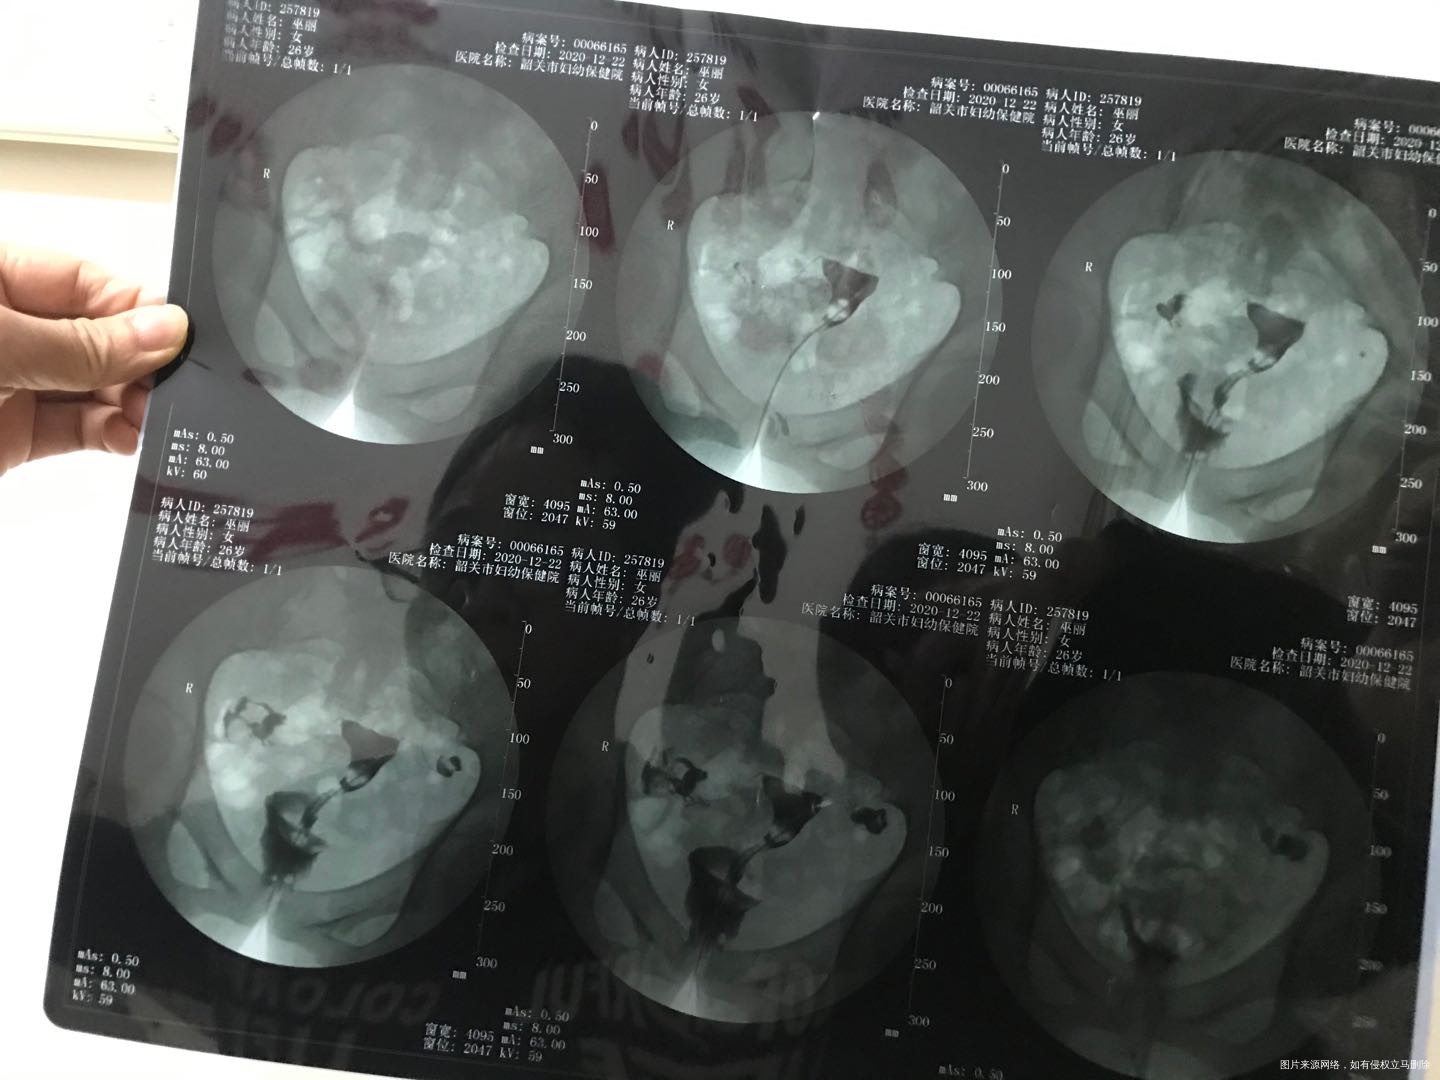

有医生看的懂造影单吗?拍的不是很清楚,麻烦帮我分析下谢谢

你好,看片子是一侧输卵管不通,一侧输卵管积水。建议试管助孕

做了输卵管造影吧,一侧不通,一侧有积水,可以尝试疏通术后备孕,但是怀孕几率不是很大,积水一侧基本上没有功能了,如果想快点,就直接试管婴儿技术助孕吧,一步到位,早点解决孩子问题。

苏占营 回复 匿名用户:移植前需要做结扎或者切除,以免影响胚胎着床。